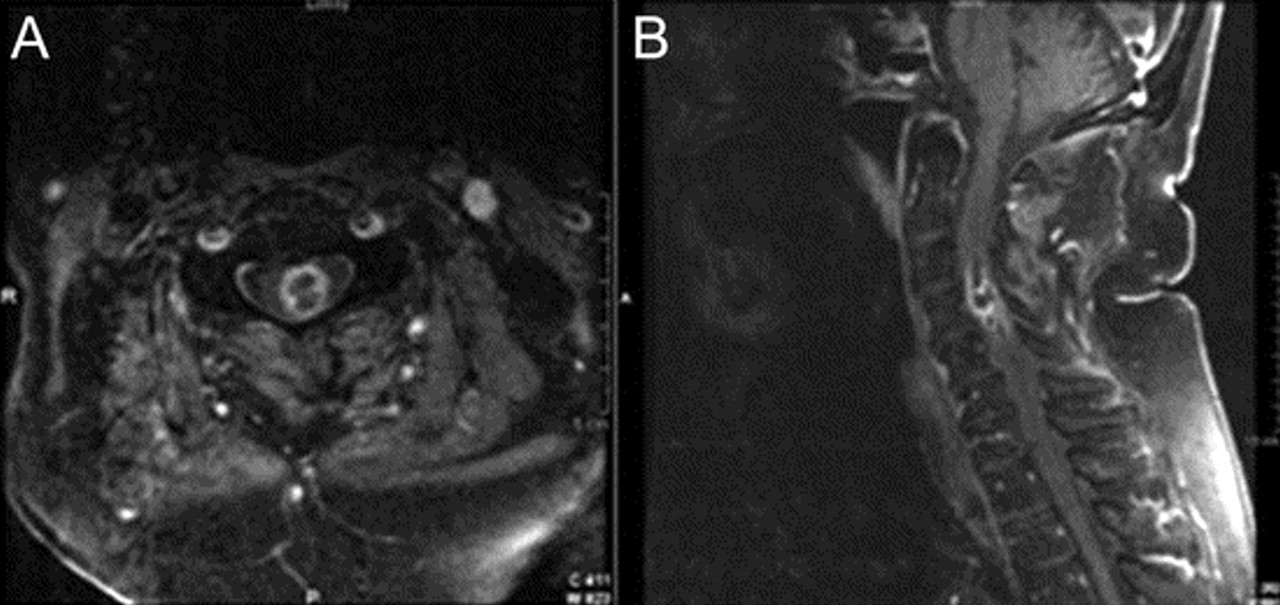

一个79岁的老人对慢性溃疡性结肠炎强的松治疗发展严重midcervical疼痛和进步的弱点在几天左胳膊和腿。这是与左前臂感觉异常和泌尿犹豫和尿失禁。他没有颅或延髓的症状。一般检查,他无热的但是有midcervical脊柱疼痛。神经系统检查发现正常的精神状态和颅神经;力量是2/5在左边,右边和4/5;对疼痛的感知水平和温度对C4的权利,减少了本体感受的左脚和手;有一个左巴宾斯基的信号和一个哑巴右足底的回应。白细胞计数为18.2×109/ L。血培养结果为阴性。胸部CT显示多个肺结节。颈椎核磁共振(图1)左边显示髓内ring-enhancing质量与水肿从C2 C7相关疼痛。脊髓切片显示开放诺卡氏菌属farcinica脓肿(图2)。腰椎穿刺和支气管镜检查没有进行。病人甲氧苄氨嘧啶IV和地塞米松治疗。10天后,下肢力量改善双边。左手臂力量和感觉赤字保持不变。他8周后死于心脏骤停。不需要进行尸检。